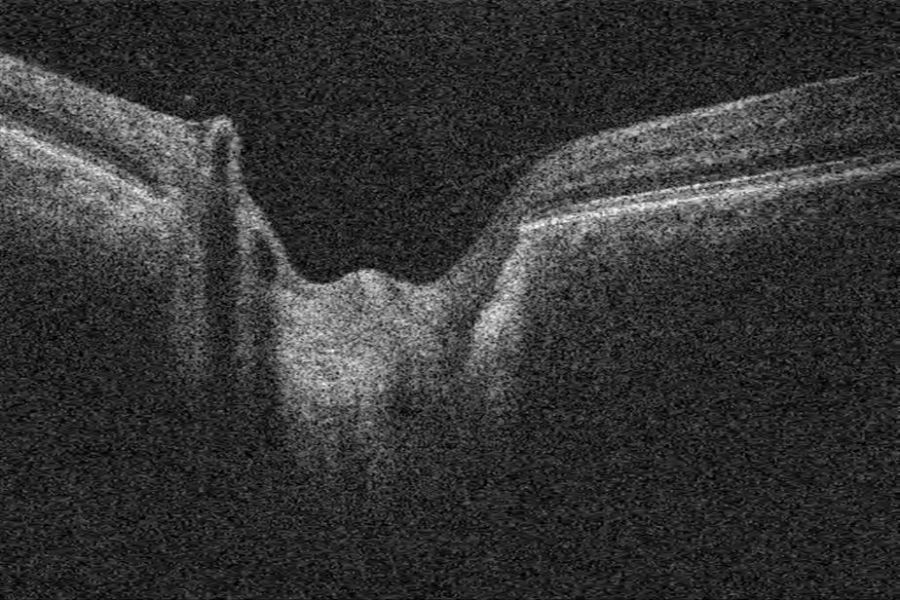

Grubenpapille (siehe Anmerkung)

Papillengrube (аббревиатура: Grube)